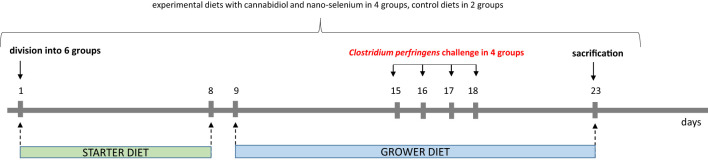

A total of 360 one-day-old male broiler chicks were purchased from a local hatchery. Upon arrival, the broilers were divided into six treatment groups with eight replicate cages of nine chickens per group according to average body weight. The conditions, such as temperature, light cycle and humidity, were maintained according to standard management practices for commercial chicken houses. Birds on days 0–8 were fed a starter diet, and a grower diet on days 9-23, which was formulated to meet or exceed the requirements for broiler chickens. The basal grower diet was based on wheat (50.76%), soybean meal (21.76%), triticale (15.54%), fish meal (5.18%), and rapeseed meal (4.15%) (ref. 32), which made the gut environment favorable for C. perfringens growth. Birds in the negative control (I, C) and positive control (II, C. perfringens) groups consumed a basal diet throughout the experiment. Groups CBD + C. perfringens (III) and nano-Se + C. perfringens (IV) were challenged and supplemented (on top) with 15 g/kg Cannabis sativa extract or with 0.3 mg/kg nano-Se. Chicks from CBD + nano-Se (V) group and CBD + nano-Se + C. perfringens (VI) were fed a control grower diet supplemented with both additives, but the second group was challenged with C. perfringens. The division into groups is shown in f1. A simple study design is shown in f2.

Clostridium perfringens challenge and sample collection

Before the C. perfringens challenge, 1 mL of a coccidial cocktail was administered to all birds at 14 and 15 days of age to create a favorable gut environment for C. perfringens colonization (ref. 32). The birds were given C. perfringens in four challenged groups at 15, 16, 17, and 18 days of age. Briefly, after 4 hours of food deprivation, animals in C. perfringens, CBD + C. perfringens, nano-Se + C. perfringens, and CBD + nano-Se + C. perfringens groups were given (per os) 1 mL of inoculum (brain–heart infusion medium) containing approximately 108 CFU/mL C. perfringens type A strain 56 bacteria, which was isolated from infected chickens, according to the previous protocol (ref. 32). The birds in the C and CBD + nano-Se groups were each administered 1 mL of sterilized broth medium.

On day 23, the birds were weighed, and eight broilers from each group were electrically stunned (150 mA, 350 Hz) and decapitated. Blood samples were collected into test tubes with an anticoagulant (heparin) from the wing vein in two replicates. One sample was for the determination of hemoglobin in whole blood, and the other sample was centrifuged at 3000 × g for 10 min, and blood plasma was collected. Subsequently, the entire digestive tract was removed from the same birds, and 1 cm long sections of the duodenum (on the flexion), jejunum (at Meckel’s diverticulum) and ileum (5 cm proximal of the ileocecal junction) were collected and placed in buffered 10% formalin solution and in a mixture of paraformaldehyde and glutaraldehyde in phosphate buffer for histological analyses. In addition, the samples of jejunum and blood were immediately frozen at -80oC for ELISA analysis.